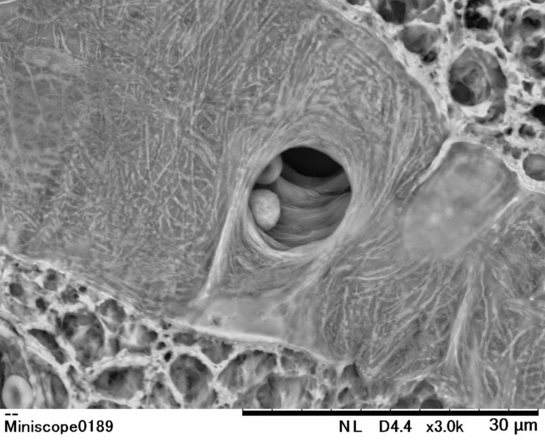

【 厚さ30 µm パラフィン切片の低真空走査型電子顕微鏡画像 】

Low-voltage scanning electron microscopic image of 30 µm-thick paraffin section

膵臓で観察された血管の分岐部と多数の赤血球